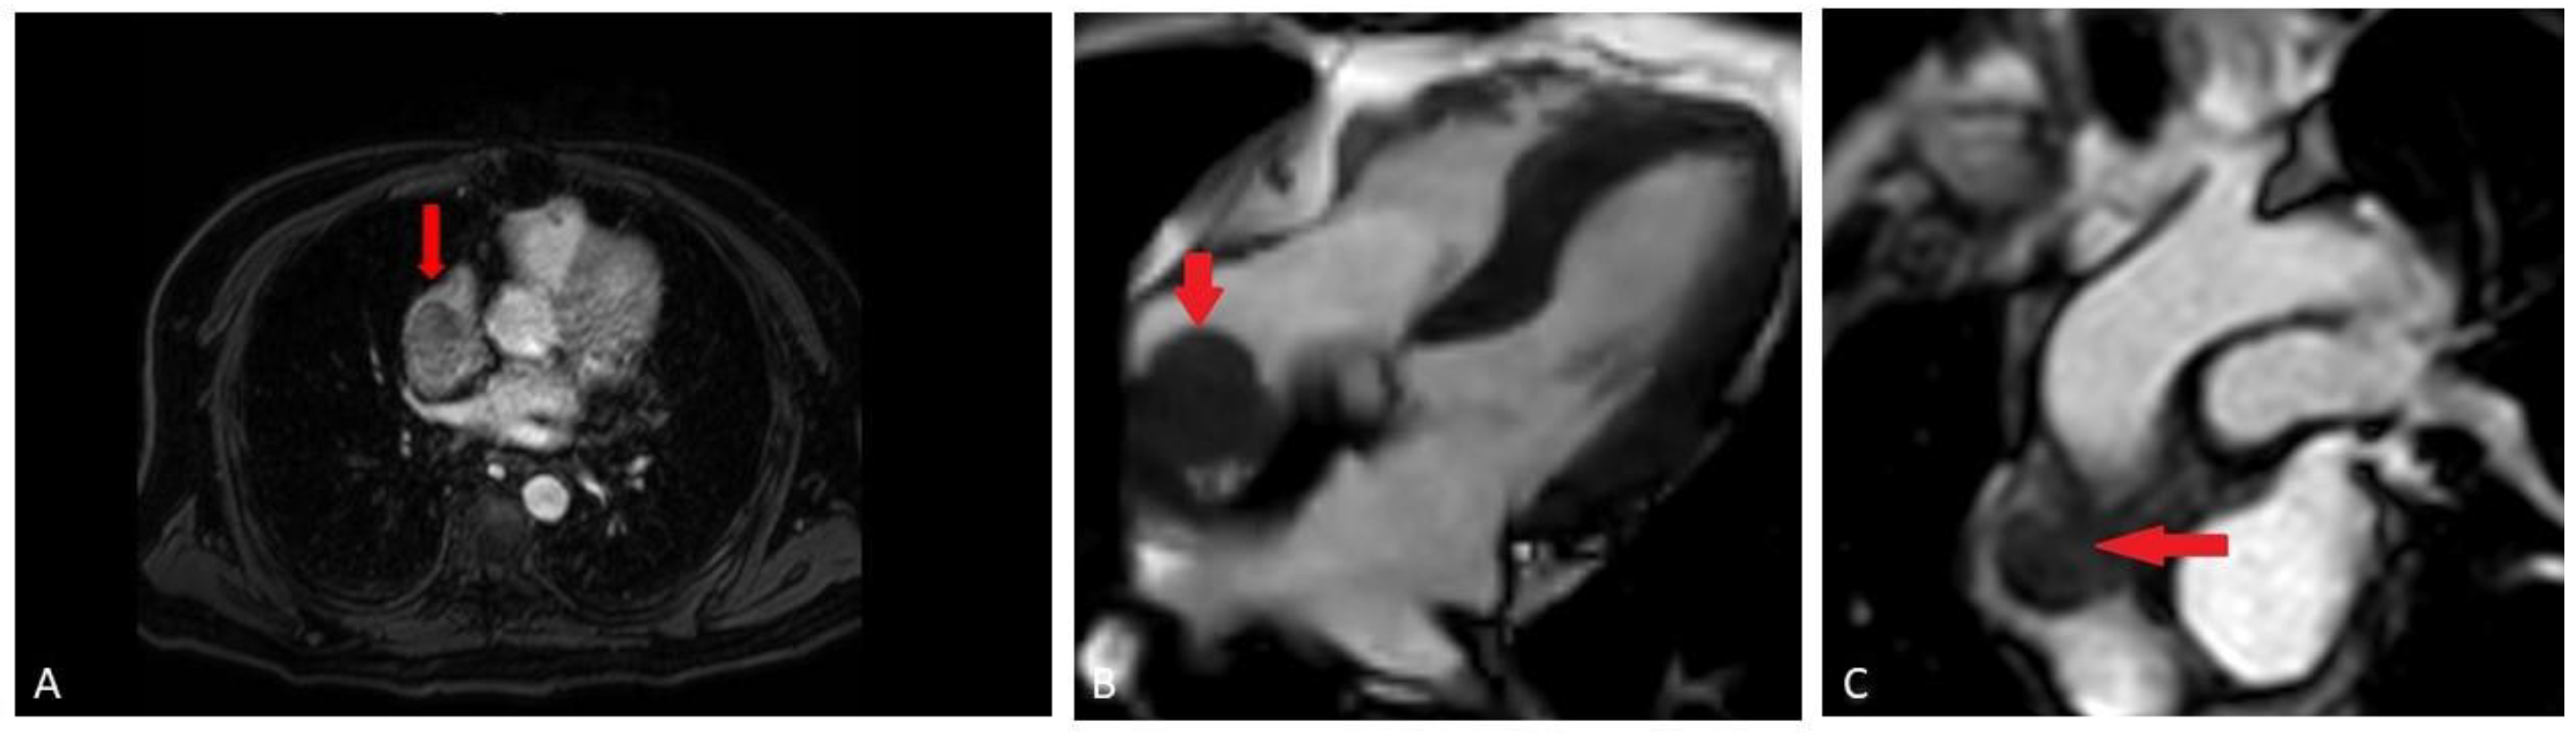

A bone scan showed a right maxillary sinus mass extending into the orbital floor, as well as increased activity from the proximal right femur to the mid shaft, and the left sacrum. A cardiac MRI revealed an irregularly shaped mass invading the superior vena cava and up to the atrial free wall (Figure 1). The X-ray of the right femur showed a large lytic lesion and multiple small lesions in the proximal right and left femur (Figure 2). Magnetic resonance imaging (MRI) of the brain and cervical spine further confirmed the right maxillary sinus mass extending through the orbital floor and into the pterygopalatine fossa and inferior orbital fissure (Figure 3).

Figure 1.

(A) Cardiac MRI early post-contrast mDixon sequence (fat suppressed gradient echo sequence), demonstrates enhancing component of the mass in the distal left Superior Vena Cava (SVC); (B) cardiac MRI pre-contrast balanced turbo field echo (BTFE) sequence, demonstrating adherent mass (red arrow) along the right atrial free wall; (C) cardiac MRI early post-contrast perfusion sequence (T1 weighted, gradient-echo), demonstrating relatively homogeneous enhancement of the mass (red arrow).